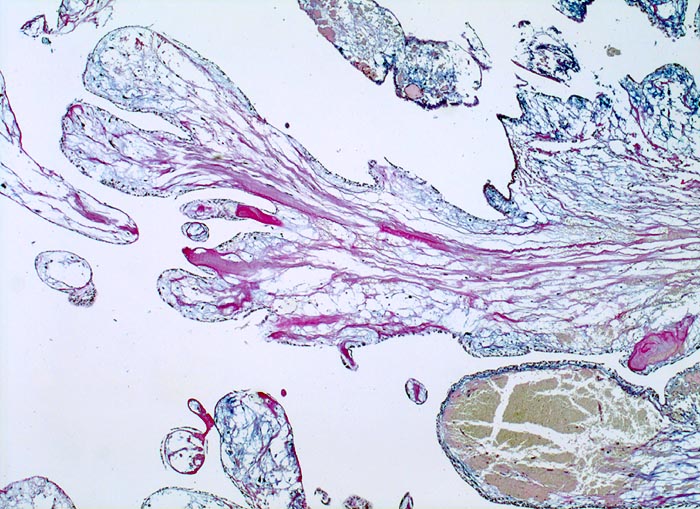

Vorhofmyxom

Makroskopie

Befund

Pathologischer Befund